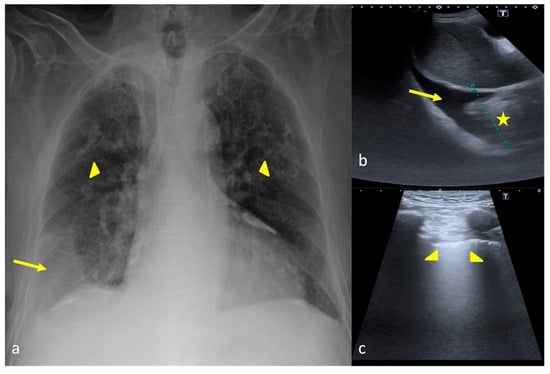

2.4. Cardiogenic Pulmonary Edema

2.5. Acute Respiratory Distress Syndrome

- Assaad, S.; Kratzert, W.B.; Shelley, B.; Friedman, M.B.; Perrino, A. Assessment of Pulmonary Edema: Principles and Practice. J. Cardiothorac. Vasc. Anesthesia 2018, 32, 901–914. [Google Scholar] [CrossRef] [PubMed]

- Wang, Y.; Shen, Z.; Lu, X.; Zhen, Y.; Li, H. Sensitivity and specificity of ultrasound for the diagnosis of acute pulmonary edema: A systematic review and meta-analysis. Med. Ultrason. 2018, 1, 32–36. [Google Scholar] [CrossRef]

| Interstitial Syndrome (Cardiogenic pulmonary edema, ARDS) | CXR showed a sensitivity of 36%, specificity of 90%, PPV of 29% and NPV of 92% while these results combined with clinical examination findings became 50%, 84%, 28% and 93% respectively. | US abnormalities may precede those of radiography and can be diagnostic, with a sensitivity and specificity of 97% and 95%, respectively. |